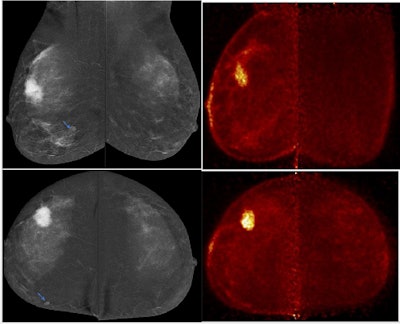

PEM detected multifocality in right breast and excluded multicentricity overestimated by contrast-enhanced mammography (left upper-outer quadrant focal heterogeneous non-mass enhancement was considered suspicious BIRADS-4). Left breast wide local excision revealed sclerosing adenosis and usual ductal hyperplasia. Follow-up revealed no residual suspicious lesions.